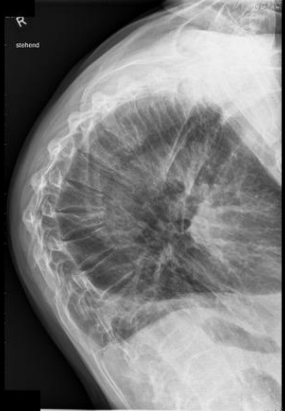

Lateral T-Spine: Eval Criteria

Thoracic vertebral bodies, intervertebral joint spaces, and intervertebral foramina

T1 to T3 will not be well demoed

Intervertebral disk spaces should be seen

Excessive rotation indicated by > 1/2” of space between separated posterior ribs

Lateral T-Spine: Is this Image Good?

No

Missing part of T1

Blurry - we want ribs blurred not the vertebrae

Ask pt to stay still while taking breaths

Separated posterior ribs indicate rotation at the superior aspect of spine

Overexposed

Decrease mAs

How does rotation manifest on a Lateral T-Spine?

Poor superimposition of posterior aspects of vertebral bodies and >0.5" of separation between posterior ribs